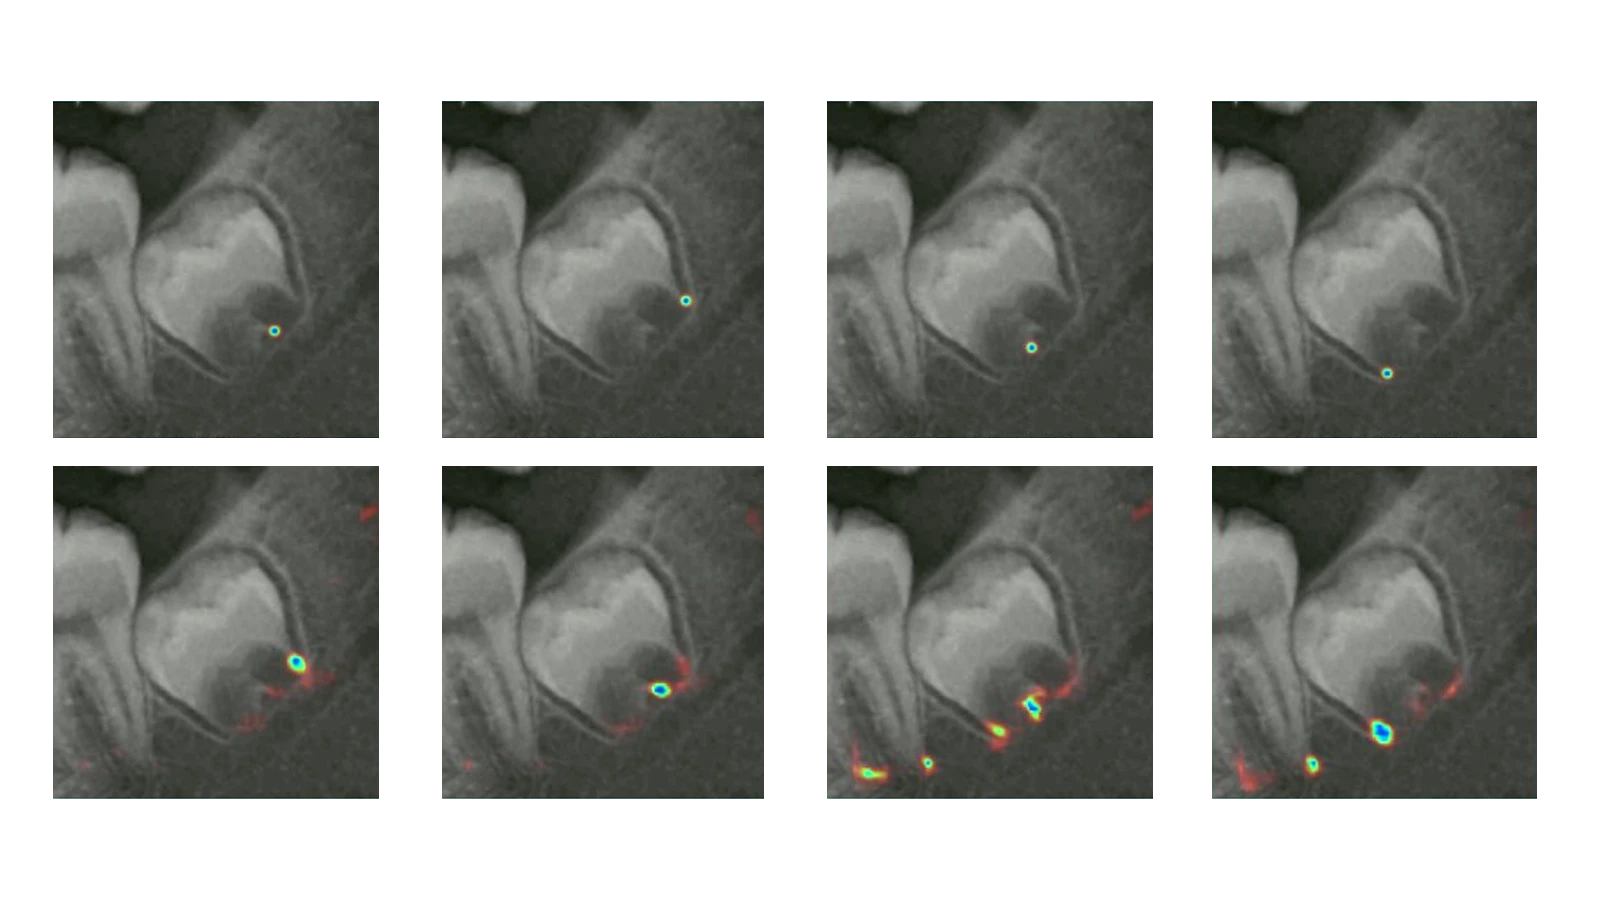

Utilize pulp-tooth area ratios from intraoral radiographs to estimate adult ages with high precision.

Leveraging state-of-the-art image processing and statistical models to deliver unmatched accuracy in age estimation.